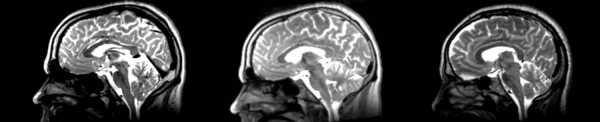

- 01053-t2 -> 01031-t2 = Result. All the images shown have the moving image on the left, the resultant image in the middle, and the target image on the right.

Rigid

01053>01031rigid.png = not bad... different brains of different sizes, but seem to be aligned in the ventricles so output seems okay. output slightly blurry. bad initial leveling displays.

Linear

01053>01031linear.png = not bad... different brains of different sizes, but seem to be aligned in the ventricles so output seems okay.output slightly blurry. bad initial leveling displays.

Affine

01053>01031_affine.png = looks good in terms of size. odd warping of frontal lobe and cerebellum area, but otherwise good coregistration.